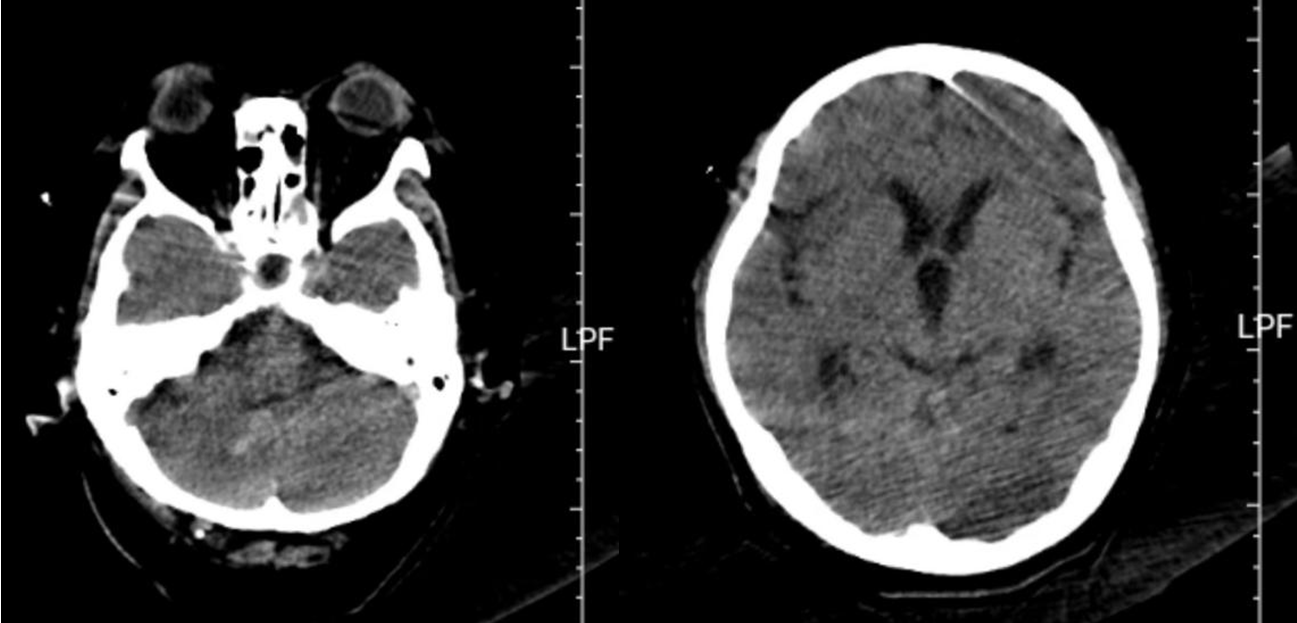

上图所示为患者出院前复查颅脑CT。

患者收治到急诊重症监护病房后,东院神经外科刘建辉主任医师、胡佳主任医师、薛昆副主任医师、吕新亭主治医师,急诊重症监护病房潘继明主任医师对患者的病情进行了全面评估,认为患者颅后窝出血量大,压迫脑干,已出现意识障碍,昏迷,血压、心率不稳等表现,随时都有心跳停止的可能,手术指征明确,但患者生命体征不稳,手术风险极大,无法耐受开颅手术。经过综合考虑,决定为患者实施微创脑内血肿穿刺引流术,征得患者家属同意后,立即开通“绿色通道”,快速完成术前准备,紧急将患者送至手术室。麻醉科尚书军主任医师评估病情后为其进行了全身麻醉并更换喉罩为气管插管。手术医师首先在患者右侧额部发迹内头皮切开约3mm的切口,快速进行侧脑室穿刺手术,释放血性脑脊液,解除了患者脑积水病情,为后续小脑出血手术争取时间,然后调整体位,根据术前影像检查进行血肿穿刺规划,沿穿刺点精准置入引流管1根,术中抽出血肿15ml,手术快速顺利完成。术后在急诊重症监护病房及神经外科医护人员的精心呵护下,患者逐渐恢复意识,术后3周完全恢复正常,顺利出院。